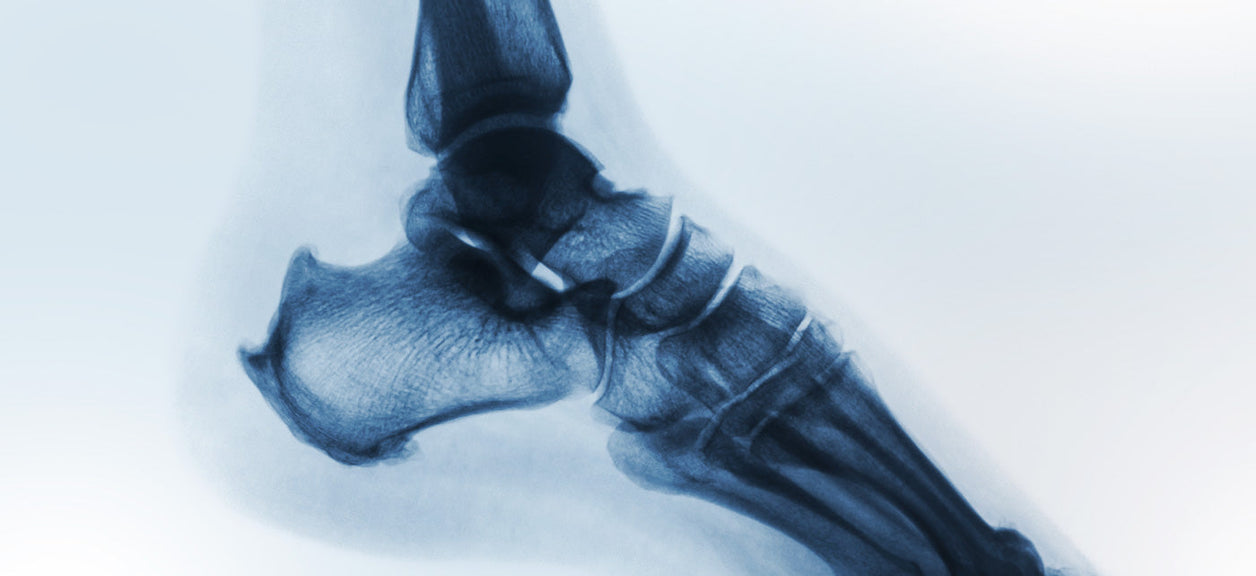

Fractures and Osteoporosis

Osteoporosis is the most common reason for fractures among the elderly. There are approximately two million osteoporosis-related bone fractures a year in the U.S., resulting in $20 billion in annual direct health costs. The consequences are serious: In addition to potentially ending the ability of an individual to live independently, the risk for death increases by as much as 20 percent.